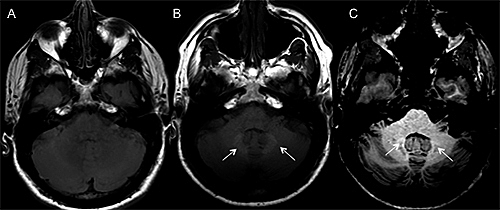

• Estudio del cerebro por imágenes.

Estudio del cerebro por imágenes.

Se fortalecen las investigaciones respaldadas por Resonancia magnética y tomografía por emisión de positrones. Permitieron la visualización de la actividad cerebral en el momento. Surgen baterías de pruebas neuropsicológicas para establecer diferentes diagnósticos.